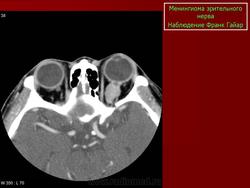

КТ-семиотика

На КТ срезах без контрастного усиления менингиома зрительного нерва выглядит изоденсной. Типично наличие линейных или точечных обызвествлений. Симптом «трамвайных рельс» отражает накопление КВ по сторонам гиподенсного зрительного нерва или наличие обызвествлений в структуре опухоли. Как правило, наиболее дистальная часть зрительного нерва, в месте его вхождения в глазное яблоко, не содержит обызвествлений.

При исследовании необходимо определить расположение бляшковидной менингиомы относительно бугорка турецкого седла и пластинки клиновидной кости, так как данный тип опухоли может распространяться интракраниально через канал зрительного нерва. КТ не позволяет адекватно визуализировать интракраниальное распространение опухоли, которое может привести к развитию двусторонней слепоты.